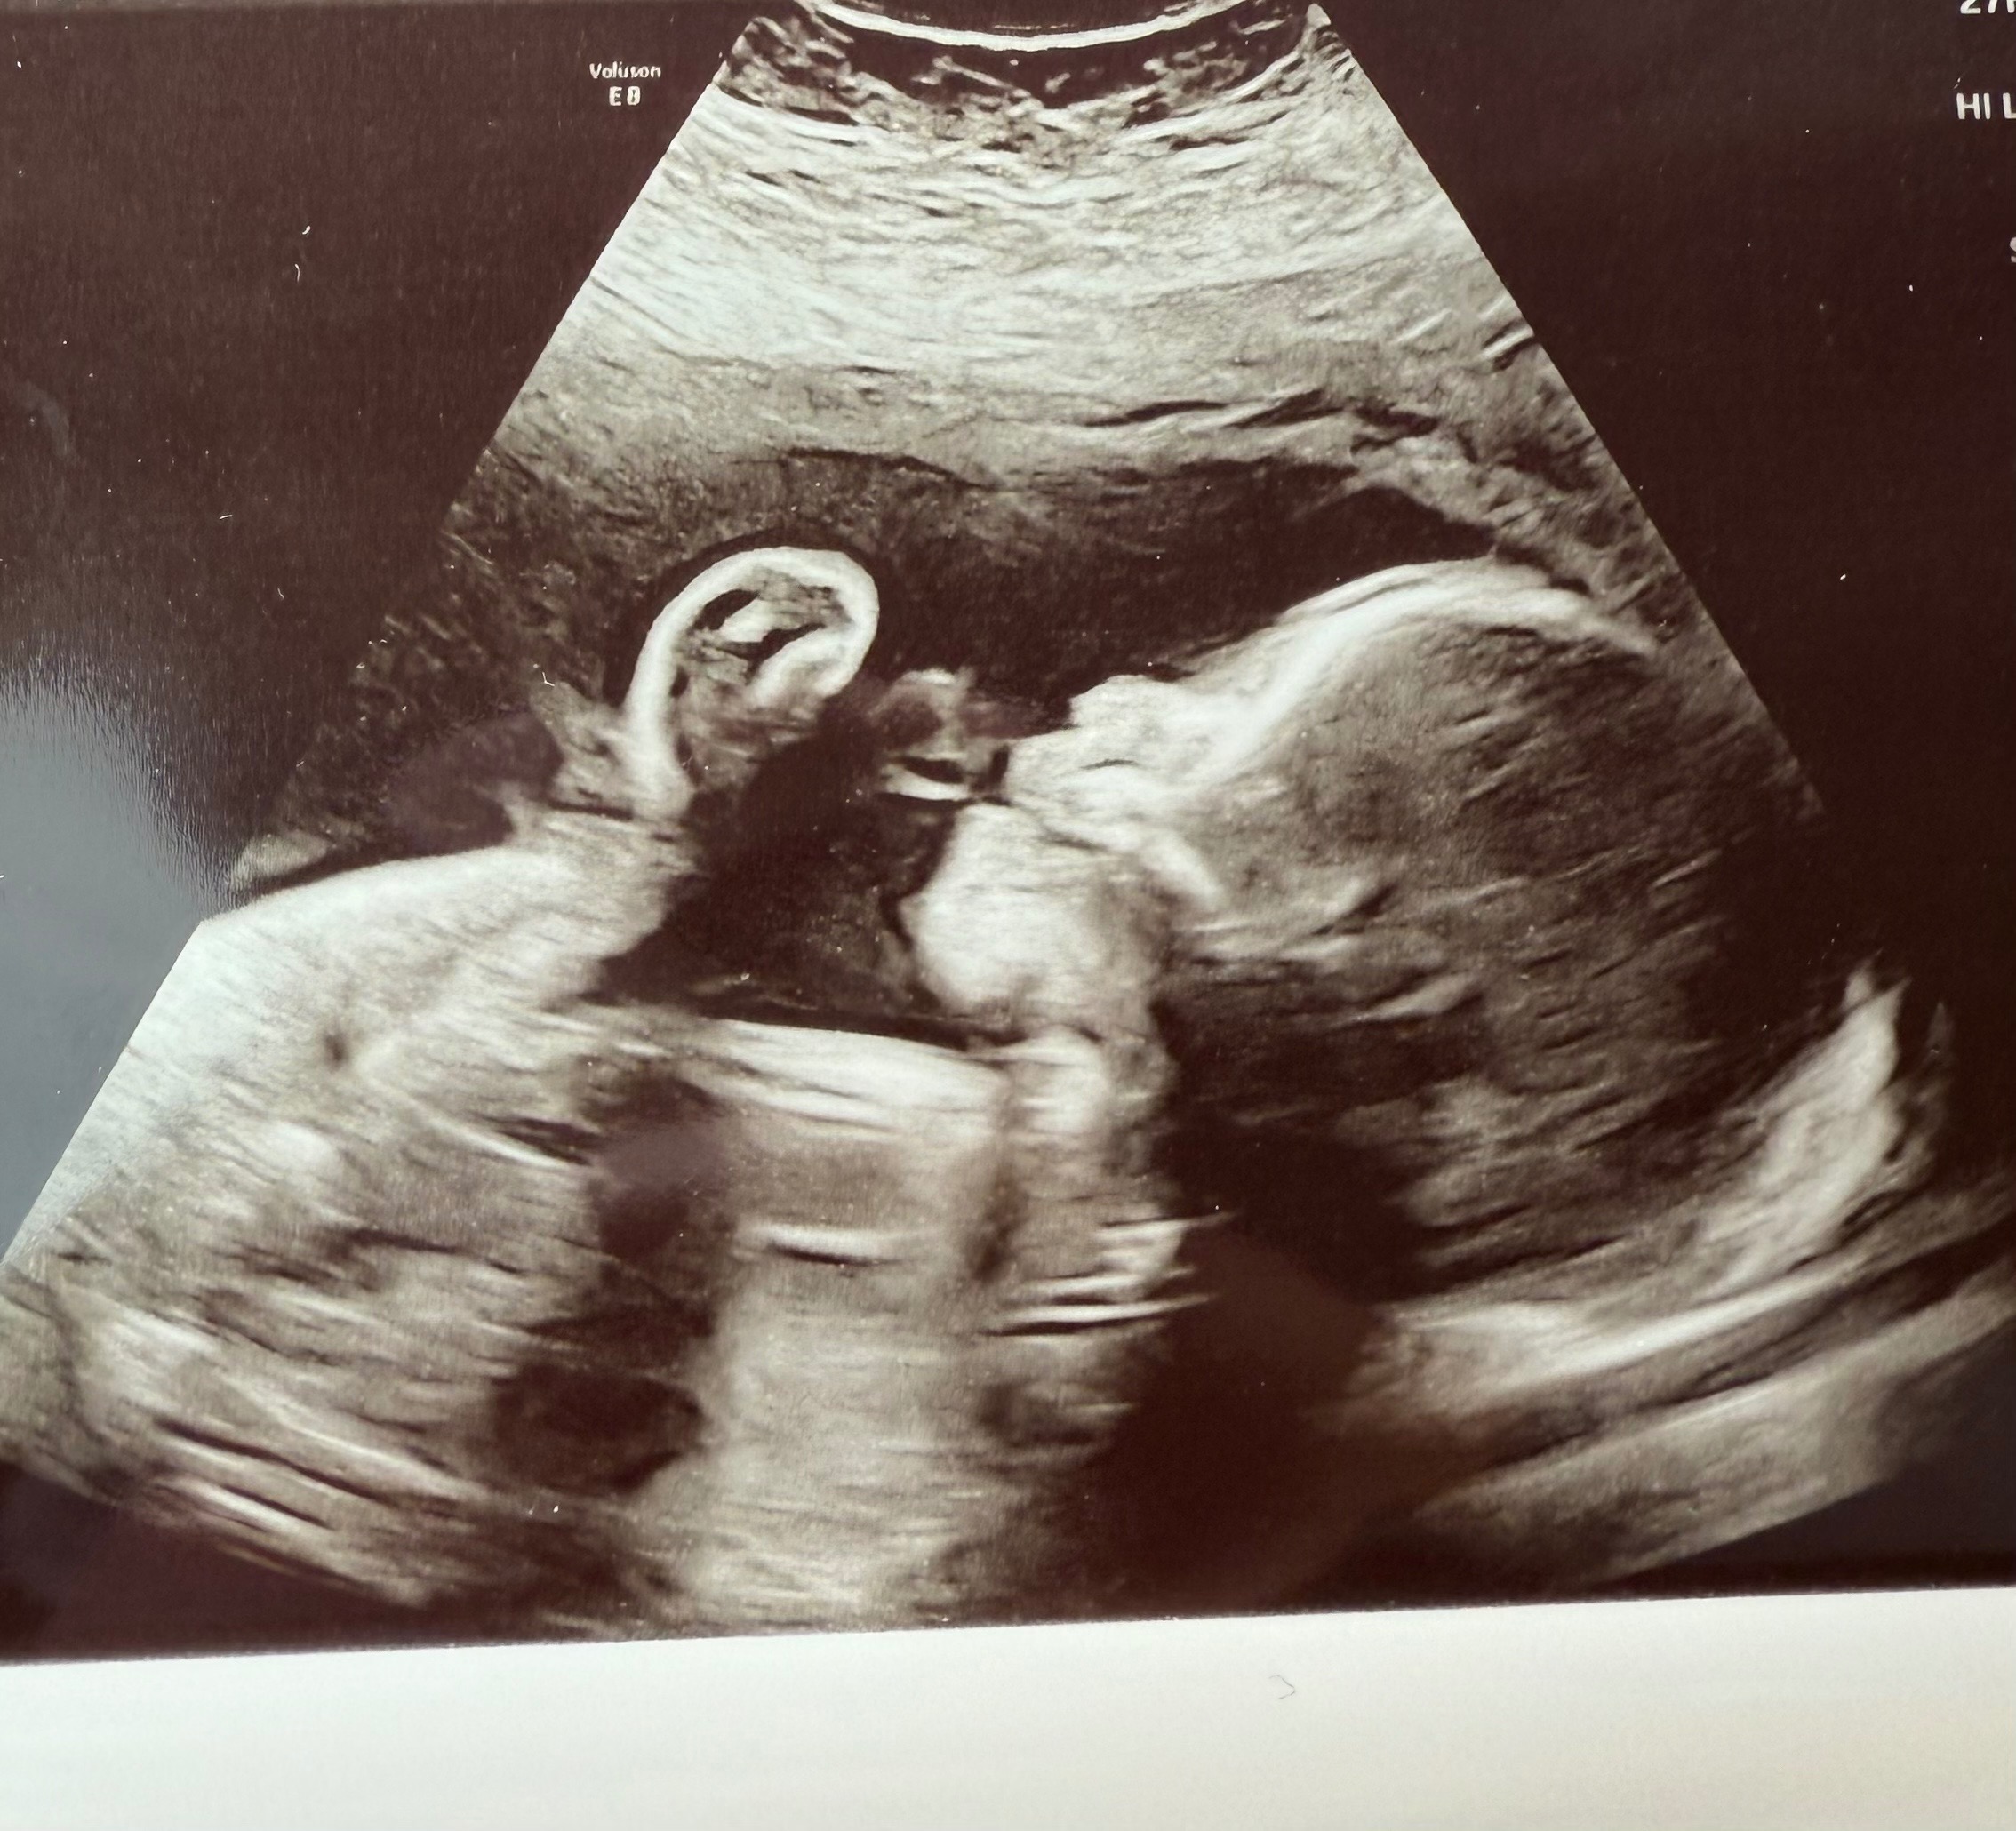

She and her husband, Edgar, are expecting their first child, sweet baby girl, Valentina. She is already so deeply loved, and we are trusting for strength, healing, and provision every step of the way. I created this GoFundMe to support them as they prepare for the medical care, surgeries, and unknowns ahead.

Valentina has been diagnosed with several complex congenital heart and organ conditions. She has Hypoplastic Right Heart Syndrome (HRHS), meaning the right side of her heart is underdeveloped. She also has Double Outlet Right Ventricle (DORV), where both major arteries come from the right side of her heart instead of being properly separated.

In addition, Valentina has Pulmonary Stenosis (PS), which means the pathway to her lungs is very narrow, making it harder for blood to flow properly.

She has also been diagnosed with heterotaxy syndrome, a condition that affects how her organs are arranged. Her stomach is on the right side, her liver sits in the middle, her intestines are rotated, and she does not have a spleen, which can affect her immune system.

Because of these conditions, Valentina will need at least two major heart surgeries, one around 3 months old and another around 3 years old, to help correct the “plumbing” of her heart and improve how it functions.

Immediately after birth, she will be transferred to the pediatric cardiac care unit at Children’s Hospital. There, doctors will perform genetic testing, an MRI, and evaluate whether her pulmonary veins are properly connected to her heart. Depending on what they find, she may need emergency surgery right after birth.